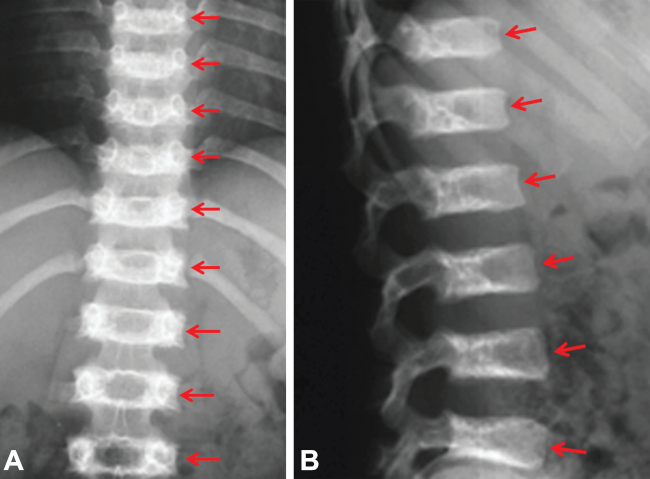

El examen radiológico de la columna verificó la presencia de vértebras con acentuada platiespondilia (importante reducción del diámetro vertical de las vértebras), hendiduras coronales y lesiones radiotransparentes (encondromas) que determinan irregularidad del platillo vertebral (►Fig. 2A y B).